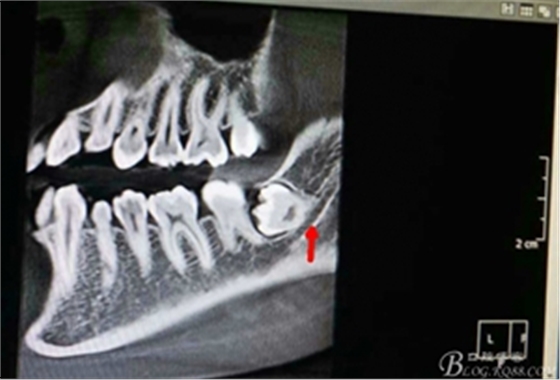

圖4.術(shù)前的CBCT縱剖面檢查:38牙根1/3緊鄰下頜管,看紅色箭頭。提示盡量不要斷根,如根尖折斷,取根導(dǎo)致下頜神經(jīng)損傷的風(fēng)險(xiǎn)加大